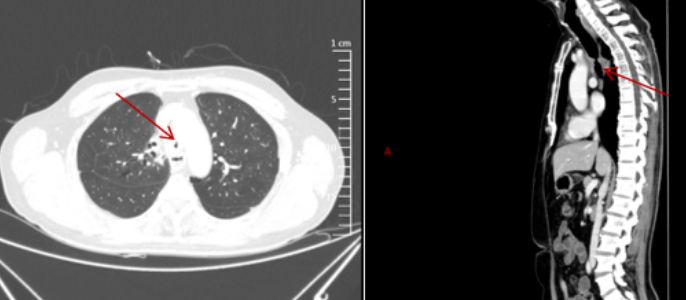

患者男性,55岁,因“气管切开术后2个月,呼吸困难10天”入院。CT检查提示气管环形狭窄(图1),最窄处仅1.53 mm,狭窄周围伴肉芽组织增生。

治疗方案:采用VV-ECMO辅助支持,经右颈内静脉-右股静脉置管建立通路,正常全身抗凝。在全身麻醉下进行支气管镜介入治疗(图2),气管镜检查期间暂时停用全身抗凝,气管镜检查后恢复全身抗凝。ECMO累计支持时间为33小时,患者未出现ECMO相关并发症

图片

1  患者CT检查